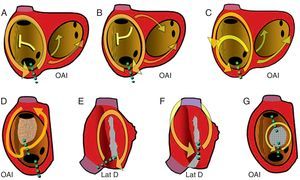

Taquicardia auricular macrorreentranteEn un mecanismo de TAMR, la activación auricular se produce de un modo continuo, sin interrupción, por un frente que rota en torno a un obstáculo formado por estructuras anatómicas (orificios valvulares o venosos), cicatrices o áreas de bloqueo funcional (anisotrópico) (Figura 7). El diámetro del circuito debería ser ≥ 2 cm para poder cartografiarlo correctamente con las técnicas de electrofisiología actuales, y circuitos más pequeños serían difíciles de distinguir de mecanismos focales1.

Figura 7. Esquemas de taquicardia auricular macrorreentrante de aurícula derecha observables en la clínica. En la visión oblicua anterior izquierda de la aurícula derecha se muestran los orificios de las cavas y el seno coronario y la cresta terminal (rayado vertical). Las flechas indican la dirección de la activación. Las líneas de puntos verdes marcan los istmos críticos de cada circuito, objetivo de ablación. A: aleteo auricular típico. B: aleteo auricular típico inverso. C: aleteo auricular típico con conducción a través de la cresta terminal. D: taquicardia auricular macrorreentrante con zona inexcitable de bajo voltaje no quirúrgica. E: taquicardia auricular macrorreentrante de cicatriz sin incluir la cava superior. F: taquicardia auricular macrorreentrante con istmo entre dos cicatrices e incluyendo la cava superior. G: taquicardia auricular macrorreentrante en torno a parche septal. Lat D: lateral derecha. OAI: oblicua anterior izquierda.

La alta incidencia del AA típico y su patrón reproducible en el ECG se deben a la sólida configuración anatómica del circuito, que conduce la activación circular en torno al anillo tricúspide. La activación asciende en la AD septal, gira en el techo para hacerse descendente en la AD anterolateral y finalmente pasa entre el anillo tricúspide y la vena cava inferior para alcanzar de nuevo la AD septal. El circuito se hace estable por la presencia de un gran obstáculo en la AD posterior, constituido por los orificios de las venas cavas superior e inferior, unidos por la cresta terminal (Figura 7, Figura 10).

En un 90% de los casos, el giro de la activación en el circuito de AA típico es antihorario en una visión oblicua anterior izquierda (descendiendo la AD anterior y ascendiendo la septal). Esta preferencia podría deberse a una mayor facilidad para el bloqueo de la conducción descendente en la AD septal baja, donde el miocardio es de muy escaso grosor y alineamiento irregular. Si una extrasístole se bloquea a este nivel, la conducción del frente de activación descendente por la cara anterior podría reentrar la AD septal a través del istmo cavotricuspídeo (ICT), y así se inicia el giro antihorario. El AA típico inverso (horario) recorre el mismo circuito descendiendo la AD septal y ascendiendo por la AD anterolateral, con la misma línea de bloqueo en la AD posterolateral y el mismo cierre inferior a través de ICT (Figura 7, Figura 10). El patrón de ECG es distinto del AA antihorario, con inscripción en cara inferior de deflexiones positivas melladas en forma de M y en V1 de onda negativa, ancha, mellada en forma de W (Figura 10).

Se han descrito variaciones del este circuito del AA típico en las que la activación cruza la cresta terminal a algún nivel, a la vez que gira por delante de la cava superior15, pero estas variaciones no tienen trascendencia clínica ni terapéutica (Figura 9).

Taquicardia macrorreentrante auricular derechaLas atriotomías amplias empleadas para la corrección de una comunicación interauricular o interventricular, resecar un mixoma o reparar una válvula tricúspide pueden crear un obstáculo suficiente para constituirse en obstáculo central de una TAMR, que se localiza generalmente en la pared anterior o lateral de la AD. Menos frecuente es la TAMR en torno a un parche de cierre de una comunicación auricular (Figura 7). Aunque infrecuentemente, se puede encontrar a veces zonas inexcitables, indicio de cicatriz, en la pared lateral de la AD, como base de una TAMR, en pacientes no sometidos a cirugía (Figura 7)18, 19. Se ha postulado que estas áreas de bajo voltaje, de naturaleza hoy por hoy desconocida, podrían reflejar zonas de fibrosis.

En su forma más sencilla, la TAMR de cicatriz es un circuito localizado en la pared lateral de la AD, en cuyo centro hay una línea de bloqueo, constituida por la misma cicatriz (Figura 6, Figura 7, Figura 11). El punto de giro inferior localizado entre el extremo de la cicatriz y la vena cava inferior es estrecho y suele ser una zona de conducción lenta. El punto de giro superior puede ser el extremo de la cicatriz o el orificio de la cava superior, que se puede integrar funcionalmente en el obstáculo central (Figura 6, Figura 7). En aurículas muy dilatadas, especialmente tras la cirugía de Fontan, se puede encontrar zonas inexcitables, de bajo voltaje, en las paredes de AD (Figura 11) que contribuyen a canalizar los circuitos de TAMR21, 22, 23. En pacientes sometidos a cirugía de Mustard o Senning, a la complejidad de las barreras cicatriciales se añade la enorme dificultad de acceso a las porciones de las aurículas aisladas por los parches utilizados para reconducir el flujo sanguíneo24, 25.